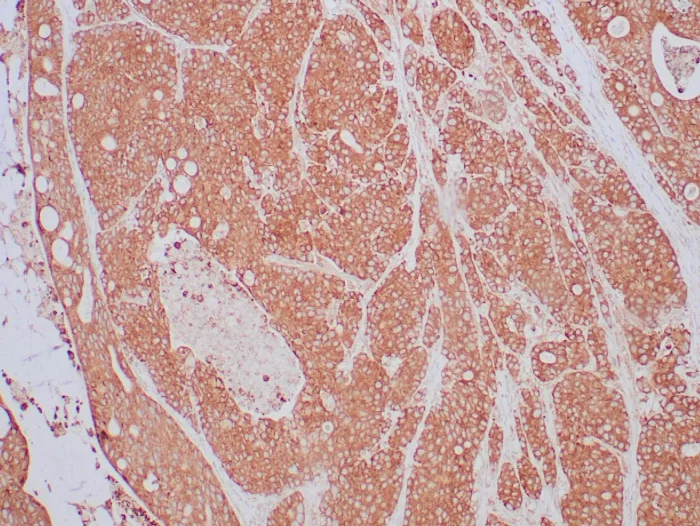

Formalin-fixed, paraffin-embedded human lung carcinoma stained with NTRK2 / TRKb Mouse Monoclonal Antibody (NTRK2/4673). HIER: Tris/EDTA, pH9.0, 45min. 2°C: HRP-polymer, 30min. DAB, 5min.